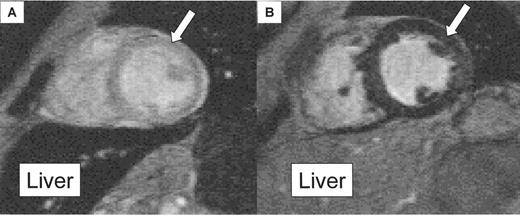

Cross-Sectional Study of Cardiac Iron Between Deferiprone and Desferrioxamine

A cross-sectional study was performed comparing myocardial T2* and LV function between 2 cohorts of thalassemia patients: one treated with standard DFO therapy, and one treated with DFP.12 The median myocardial T2* was significantly higher in the DFP group, and their ejection fraction was also significantly better (Figure 6 ), suggesting less cardiac iron and better ventricular function than in patients treated with DFO. The liver T2* was higher in the DFO group, suggesting more rapid removal of iron from this organ than with DFP. These data require prospective confirmation in randomized controlled trials (these are now underway and will be reported in late 2004 or 2005), but the current data suggest that oral DFP may have preferential access to the heart, in which case it has a potentially unique and valuable role in the treatment of iron overload.